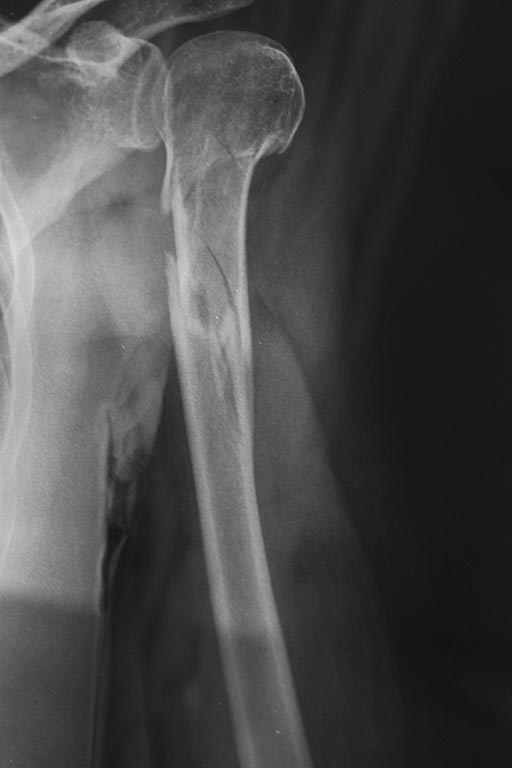

[Ortho] Перелом проксимального одела плечевой кости

Прошу прощения! Не все фотографии прикрепились. Высылаю еще фото.